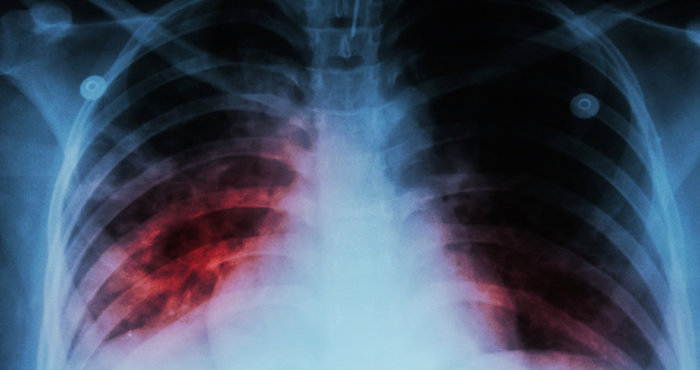

Londres, 5 de noviembre (EFE).- Casi la mitad de los casi diez millones de pacientes con tuberculosis activa (TB) diagnosticados cada año podrían curarse con tratamientos más cortos que los actualmente recomendados, según un estudio publicado hoy en Nature Medicine.

Un nuevo análisis de la Universidad de California en San Francisco (UCSF) sugiere que terapias más precisas podrían ser más efectivas a la hora de tratar la TB (una infección bacteriana), que mata cada año a unas 1,3 millones de personas en todo el mundo.

En el estudio -encabezado por Marjorie Imperial, una estudiante licenciada en Ciencias Farmacéuticas de la UCSF-, se analizaron otra vez los datos obtenidos en tres importantes pruebas que fracasaron en demostrar la eficacia de los tratamientos de cuatro meses de duración para tratar esta infección que ataca los pulmones.